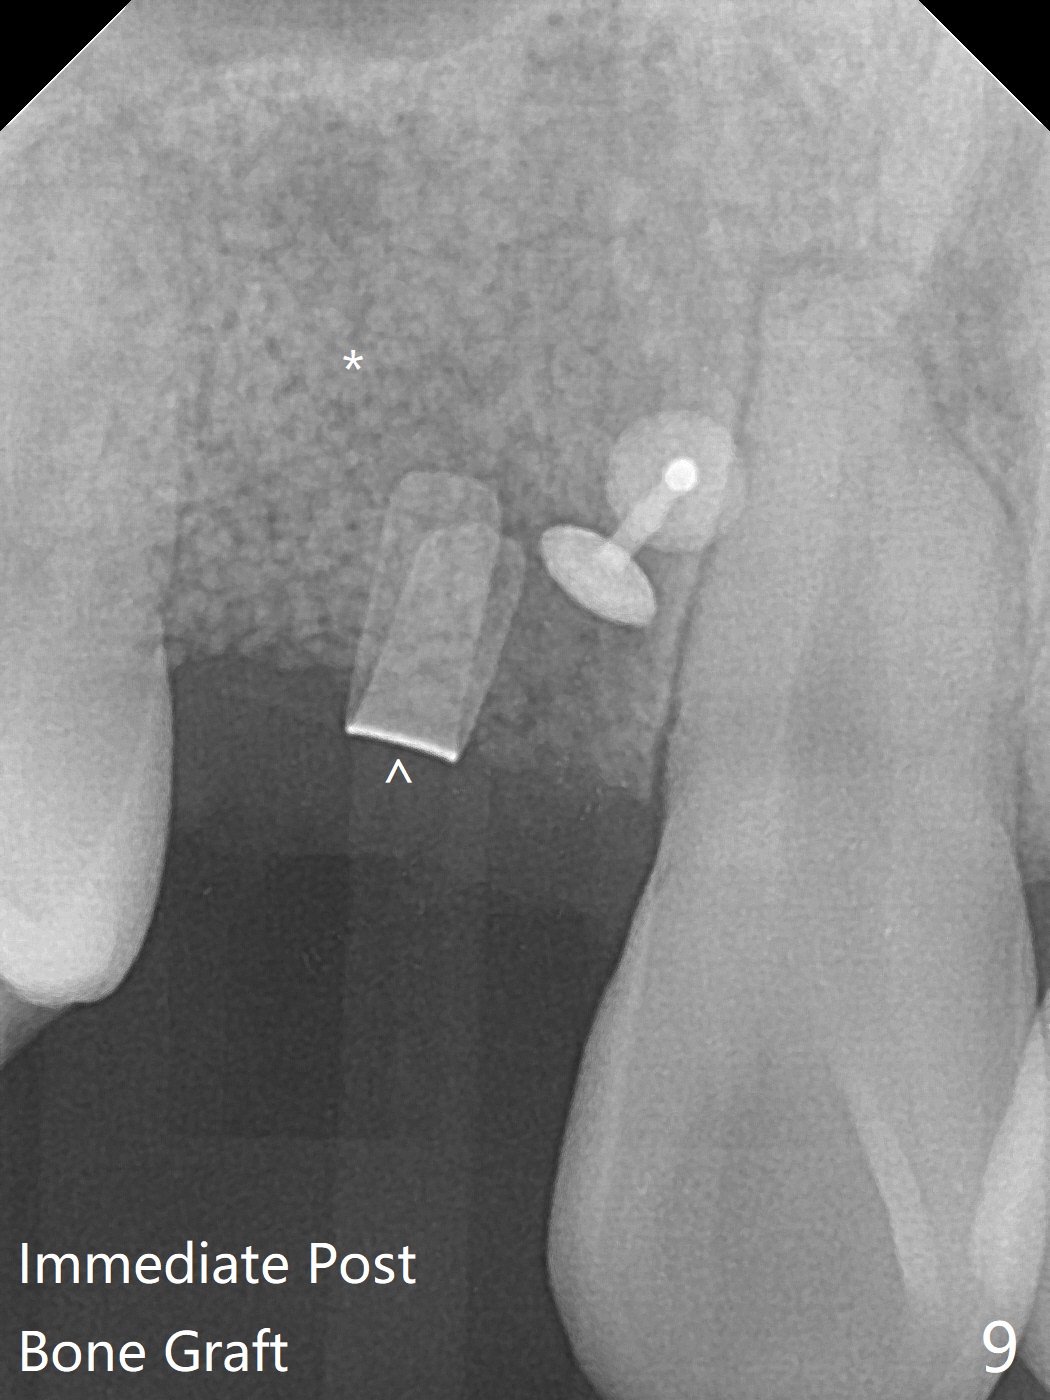

18岁男从外州大学回来,无症状,但是6号牙(右上尖牙)颊侧瘘道(图一,二(角化龈充分(箭头))),根尖片显示植体近中骨吸收(图三:*),而对侧植体仿佛骨整合(图四)。患侧切开后发现植体颊侧暴露,松动。拔除后骨缺损由粘性骨粉修复(图七,九:*),覆盖PRF膜(图七:P)和带钛网(图九:^)不可吸收膜(图五-七),后者用两个小钉子固定(图六(腭侧),七(颊侧),九),使用新的刀片和一个特殊尖头剥离器在颊侧骨膜下相当广泛分离,使用PTFE缝线,粘膜下水平褥式缝合之后(图八:箭头),多个垂直间断缝合,两个乳头垂直褥式缝合。术后一周伤口没有裂开,术后疼痛肿胀已经消退(图十)。术后十八天牙槽嵴仿佛比对侧还要宽(图十一,三与图十二,四(取模)对比)。术后5.5个月伤口没有裂开,牙槽骨,角化龈宽(图十六),与钛网和两个小钉子固定有关(图十五,十七)。CT显示牙槽骨只能容纳2.5或者3.0毫米植体(图十八)。11号牙植体牙冠粘固后没有骨质吸收(图十九),其实10,11号牙颊侧骨板隆起(图二十至二十二),而6植体失败,颊侧骨板吸收,甚至累及5号牙(图十七)。